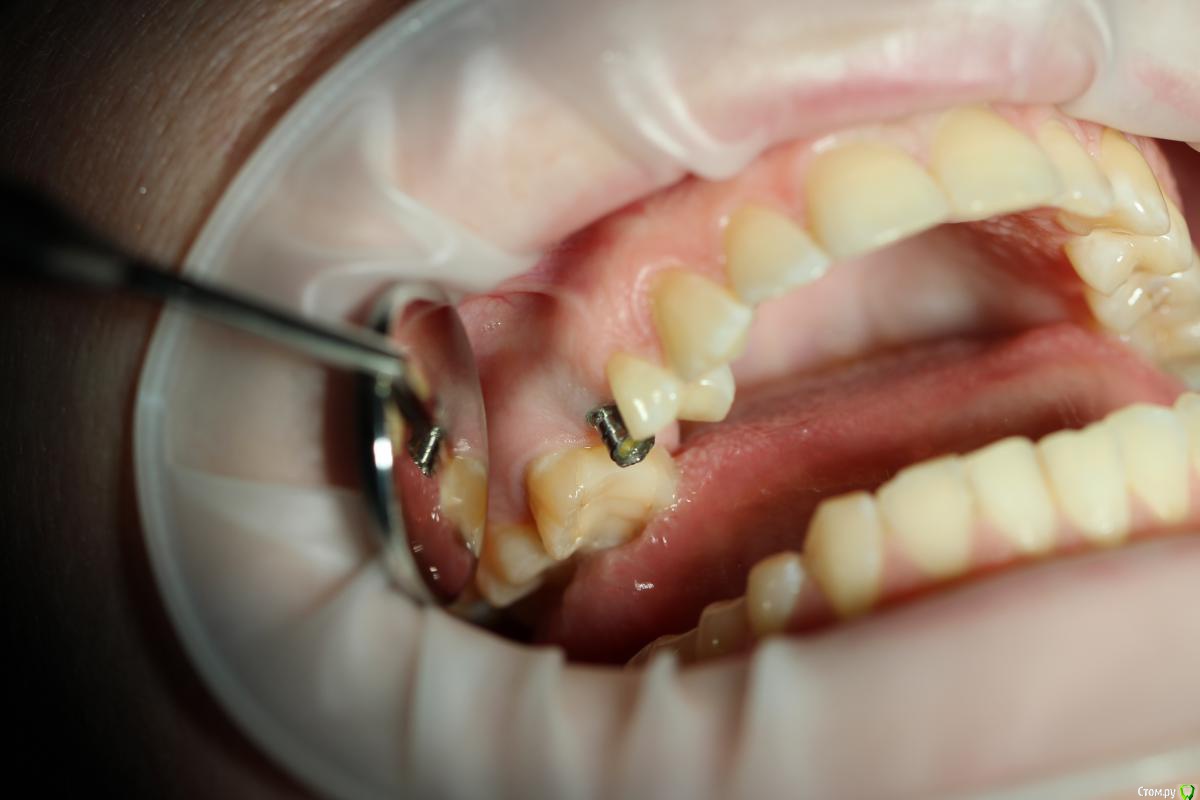

Dr. Khurtsilava Опубликовано 25 октября, 2015 Поделиться Опубликовано 25 октября, 2015 Пациентка обратилась в клинику с жалобами на отсутствие коронки на имплантате 15 в течение года (ставила в другой клинике, клиника закрылась, «голый» Nobel CC остался во рту); наличие дефекта с щечной стороны.Объективно, с щечной стороны обнаруживается дефект альвеолярного гребня в/ч в области имплантата 15 в вестибулярно-язычном направлении; отсутствие коронки на имплантате 15.Манипуляции:1 – забор ССТ с неба конвертной методикой по Зуккелли (спасибо «Доктуру» за это).2 – ушивание непрерывным замыкающим швом Prolene 5-0; лоскут обезжирен – отдыхает в физ. р-ре.3 – в области имплантата внитрибороздковый разрез, ослоение, мобилизация лоскута, деэпителизация сосочков, установка Формирователя Десны, подшивание ССТ, фиксация, ушивание лоскута в области сосочков двойным петлевым швом Prolene 5-0.Рекомендации: гигиена полости рта, мягкая зубная щетка CuraProx 5460, полоскание Curasept 0,2%, солкосерил дентальная адгезивная паста в донорской зоне и зоне реципиента, найз 2т 2р/д утром и вечером 4 дня.На 7 сутки снятие швов, соблюдение рекомендаций.Пациентка по семейным обстоятельствам пропала на пол года, явилась вчера на продолжение лечения.Вот такой вот приятный десневой рекол с врем коронкой) 10 Ссылка на комментарий